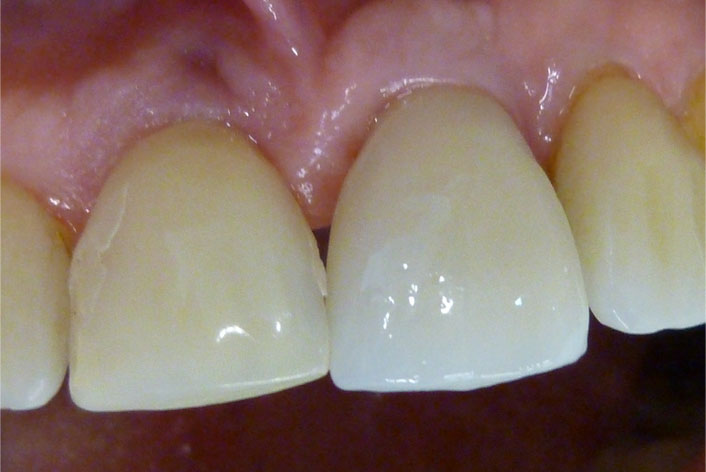

En estos casos han sido tratados con la filosofía de all-at-once, en la

misma sesión: